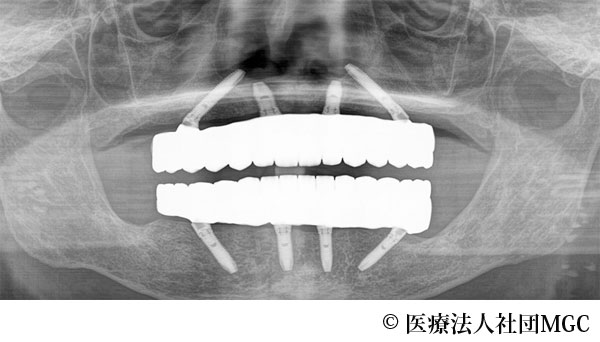

【症例1】上下All-on-4(オールオンフォー)

- 治療後

- 治療名

- 上下All-on-4(オールオンフォー)

- 費用

- 5,915,800円(税込)

- 期間

- 8ヵ月

患者様の症状

歯がボロボロで食事が困難であるとご来院されました。

治療法

ご相談の結果、患者様の生活の質(QOL)を向上させ、しっかり噛めるように上下All-on-4(オールオンフォー)を行いました。

治療結果

機能性、審美性ともに改善し、満足していただけました。

※治療結果は患者様によって個人差があります。

治療を行う上での注意点(リスク・副作用)

インプラント周囲炎の可能性、まれに歯が欠ける可能性があります。